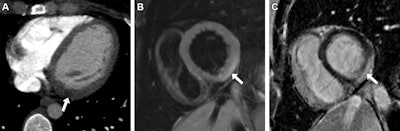

Acute myocarditis in a 30-year-old woman who presented to the emergency department with chest pain and an elevated troponin level. (A) Axial intravenous contrast-enhanced chest CT image acquired to rule out a pulmonary embolism shows focal myocardial low attenuation in the left ventricle basal inferolateral wall (arrow), indicating regional myocardial edema. (B) Short-axis 1.5-tesla T2-weighted cardiac MR image acquired 2 days later shows subepicardial hyperintensity (arrow), indicating acute myocardial edema. (C) Short-axis 1.5- tesla late gadolinium-enhanced cardiac MR image shows corresponding subepicardial late gadolinium enhancement (arrow), indicating inflammation. Images and caption courtesy of the RSNA.